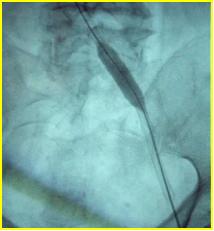

髂股静脉血栓大部分溶解,显示左髂静脉受压情况(Cockett综合征),见图5

图5